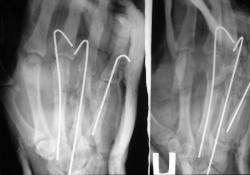

Вот еще, как по заказу сегодня случай попался

Все наоборот вставилось Недоволен первый снимок - через 1.5 мес после травмы, второй - исходный.